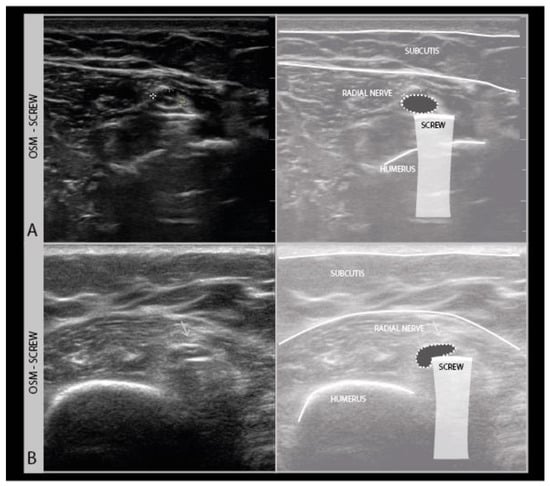

Ultrasound cannot see through air, bone, or other objects with a completely different composition than body tissue, such as bandages and plaster casts, plastic wound foil with air underneath or drains, metal wiring, or osteosynthesis screws and plates (Figure 4).

Figure 4.

Two different examples (A,B) of the radial nerve crossing over a mid-humerus osteosynthesis material (OSM) screw (high frequency −18 MHz).

While ultrasound has no inherent contra indications, good communication with the referring physician is needed to ensure that the nerve of interest is accessible for ultrasound. Fresh scars or small wounds can be scanned by covering them with a patch of transparent plastic film dressing with some NaCl or sterile gel below the film, making sure that no air bubbles remain underneath. It is also important to ensure the patient can be examined comfortably, with enough support of the affected limb and analgesia if needed.